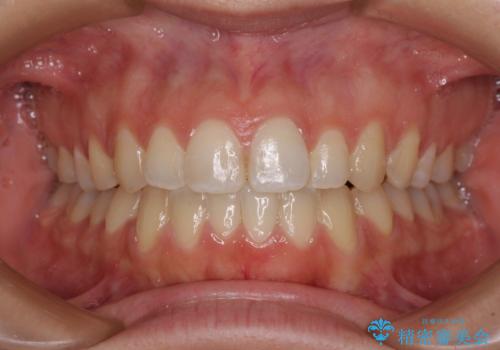

上下前歯が接触しない オープンバイトをインビザラインで改善

オープンバイト(開咬)を非抜歯インビザラインで治す